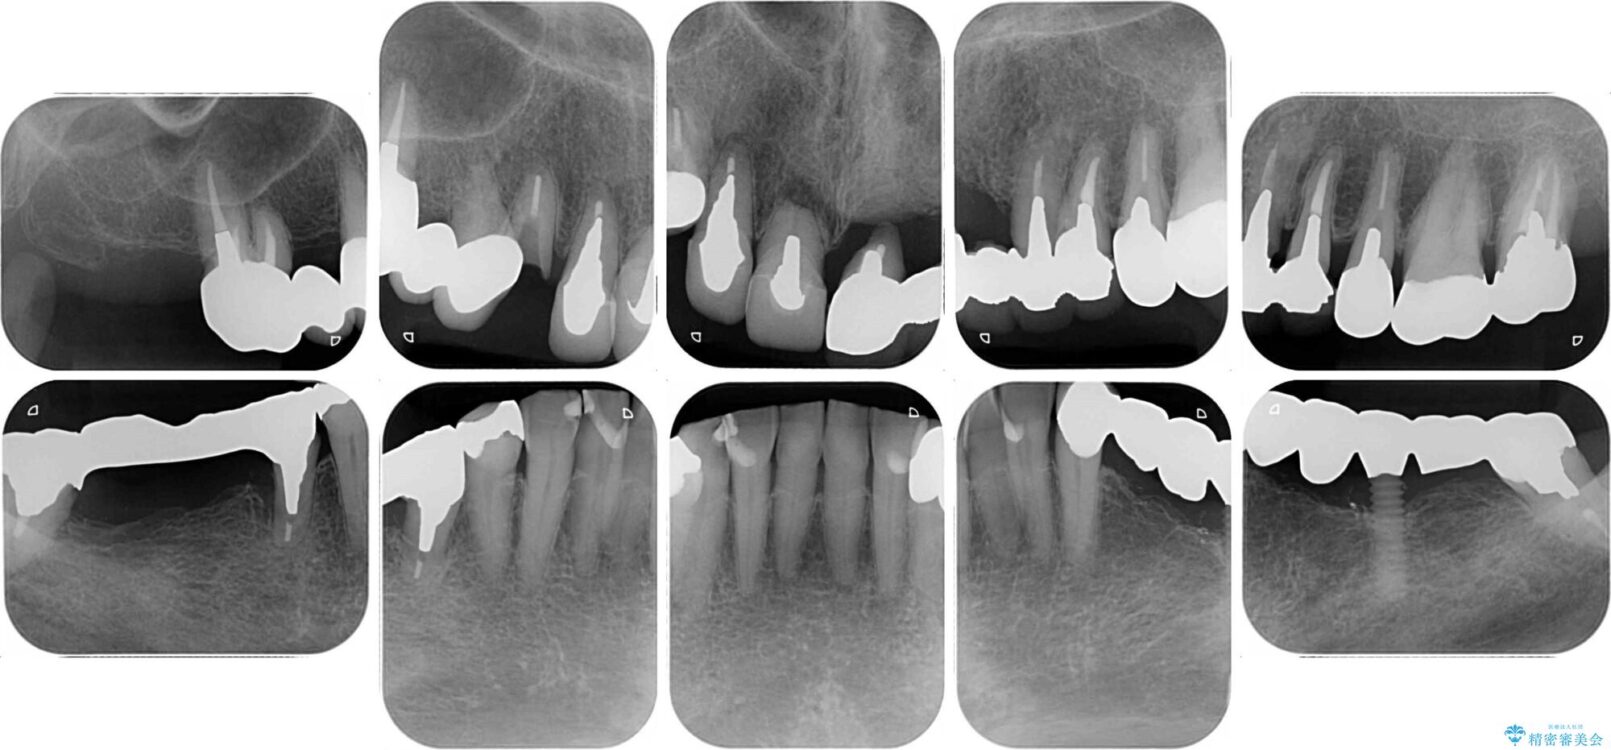

治療計画

上顎犬歯や下顎大臼歯は、必要なところはインプラントを埋入することとしました。

クラウンが不適合であったり、根管治療の必要なほどの痛みのある歯であったり、見た目の気になる前歯などをオールセラミッククラウンに補綴治療を行うこととしました。

処置を予定していた歯を仮歯に変えた時点で、下顎前歯の部分矯正を行うかどうかを尋ねたところ、折角なので行いたいと言うことでしたので、矯正治療を行うこととしました。

インプラント埋入や根管治療治療など、治癒に一定の期間を要する処置の合間に矯正治療を行うことで、効率的に治療を進めて行くことができました。